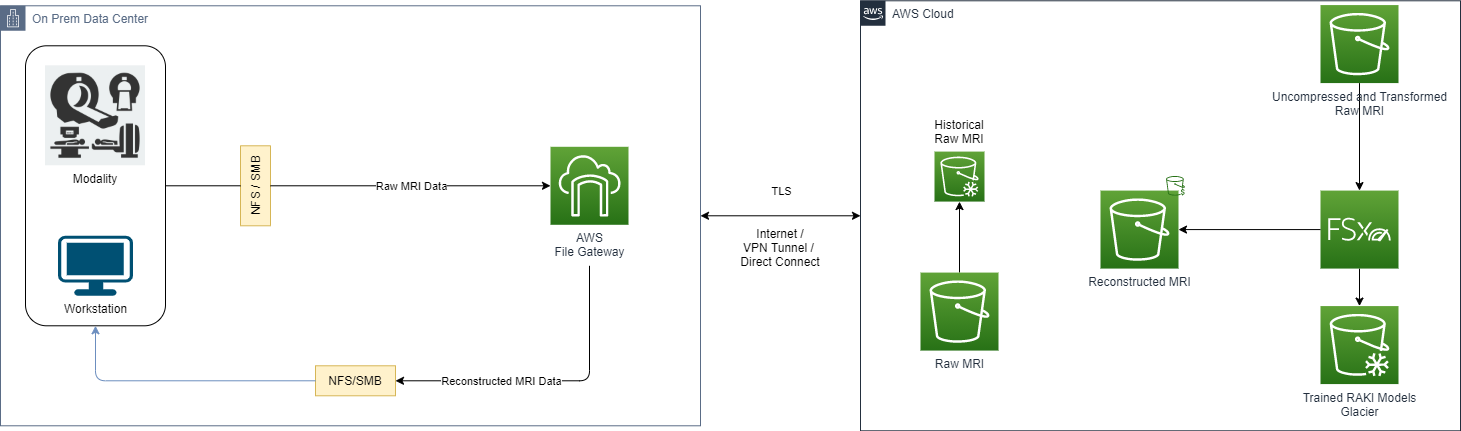

The following diagram illustrates this architecture.

This approach uses the following services:

- AWS Storage Gateway for a seamless integration with the on-premises modality that exchanges information via a file share system. This allows transparent access to the following AWS Cloud storage capabilities while maintaining how the modality exchanges data:

- Fast cloud upload of the volumes generated by the MR modality.

- Low-latency access to frequently used reconstructed MR studies via local caching offered by Storage Gateway.

- Amazon SageMaker for unlimited and scalable cloud storage. Amazon S3 also provides low-cost, historical raw MRI data deep archiving with Amazon S3 Glacier, and an intelligent storage tier for the reconstructed MRI with Amazon S3 Intelligent-Tiering.

- Amazon FSx for Lustre for fast and scalable intermediate storage used for ML training and reconstruction tasks.

The following figure shows a concise architecture describing the data exchange between the cloud environments.

Using Storage Gateway with the caching mechanism allows on-premises applications to quickly access data that’s available on the local cache. This occurs while simultaneously giving access to scalable storage space on the cloud.

With this approach, modalities can generate raw data from acquisition jobs, as well as write the raw data into a network share handled from Storage Gateway.

If the modality generates multiple files that belong to the same scan, it’s recommended to create a single archive (.tar for example), and perform a single transfer to the network share to accelerate the data transfer.